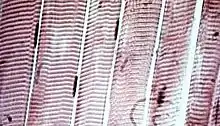

![]() The body contains three types of muscle tissue: (a) skeletal muscle, (b) smooth muscle, and (c) cardiac muscle. (Same magnification) | |

Skeletal muscle tissue is an elongated striated muscle tissue ranging from several millimeters to about 10 centimeters in length and from 10 to 100 micrometers in width.[3] Skeletal striated muscle tissue is arranged in regular, parallel bundles of myofibrils containing the many contractile units known as sarcomeres, which give the tissue its striated (striped) appearance. Skeletal muscle, is voluntary muscle anchored by tendons or sometimes by aponeuroses to bones, and is used to effect skeletal movement such as locomotion and to maintain posture. Postural control is generally maintained as an unconscious reflex, but the muscles responsible can also react to conscious control. An average adult man is made up of 42% of skeletal muscle as a percentage of body mass, and an average adult woman is made up of 36%.[4]